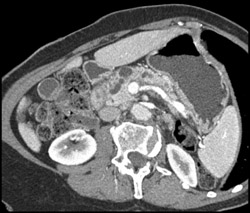

Superior Mesenteric Vein (SMV) Clot